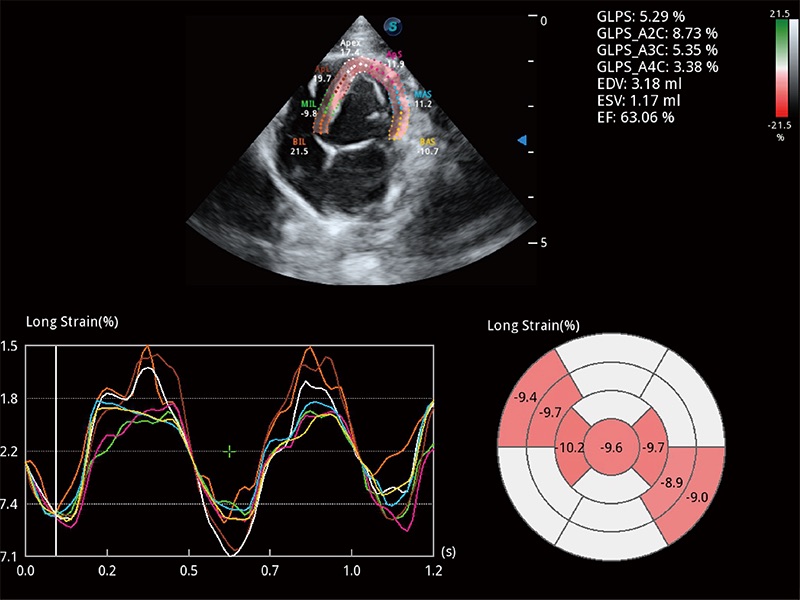

ProPet 80 配備了豐富的心臟探頭群、先進(jìn)的成像技術(shù)和專業(yè)的心臟測(cè)量工具,可幫助動(dòng)物醫(yī)生為不同體型和生理結(jié)構(gòu)的動(dòng)物提供心臟和心肌功能的全面評(píng)估。

通過(guò)心肌識(shí)別技術(shù)與二維斑點(diǎn)追蹤技術(shù)相結(jié)合,對(duì)心臟的超聲圖像進(jìn)行量化分析。計(jì)算心肌17個(gè)節(jié)段的應(yīng)變、應(yīng)變率、速度、位移等,并通過(guò)牛眼圖的形式進(jìn)行呈現(xiàn)。